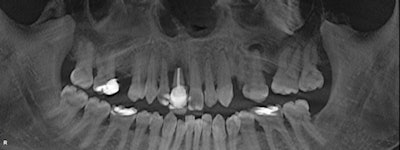

The CBCT images were impressive and became the foundation for my complete dental examination. Incidentalomas were numerous: multiple periapical pathologies and moderate to severe periodontal disease. Although he presented for his maxillary incisor, I was able to capture his attention and devise a pragmatic plan to improve the overall prognosis for his entire dentition.

A challenging road lay ahead as multiple disciplines of dentistry would be necessary to return a poorly maintained dentition to a healthy fully functioning one. Note that multiple asymptomatic periapical lesions existed with #3, #12, #13; multiple teeth were missing; and there was generalized severe periodontal breakdown.